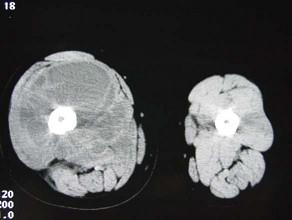

问题 男,15岁,一星期前寒战,继而体温急剧升高,达3940℃,发病后12天患肢右大腿出现功能障碍。局部出现红、肿、热、痛等症状,触之有波动感。实验室检查,血中白细胞升高,血沉增快,血培养阳性,中性粒细胞轻度升高,请结合所提供的图像,选择最佳选项 ( )

选项 A、动脉瘤样骨囊肿 B、骨巨细胞瘤 C、慢性化脓性骨髓炎 D、软骨肉瘤 E、急性化脓性骨髓炎

答案 E